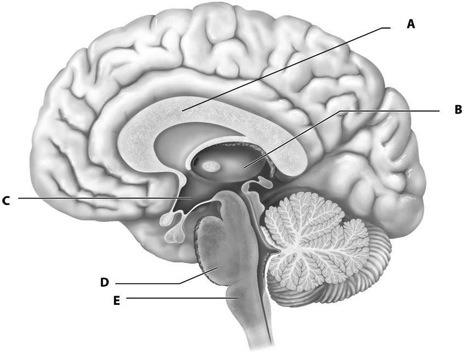

Using Figure 12.1 Match the Following

1) Medulla oblongata

2) Pons

3) Hypothalamus

4) Thalamus

5) White fiber tracts

1) E

2) D

3) C

4) B

5) A